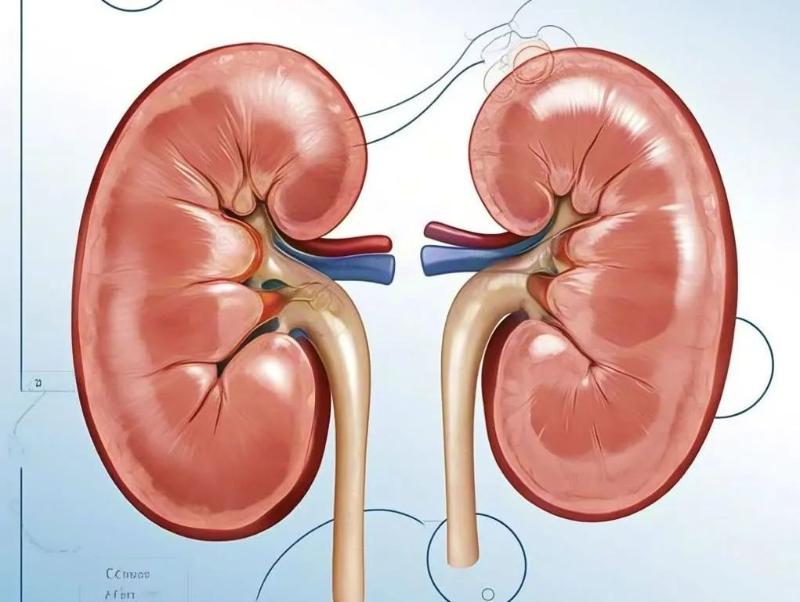

醫(yī)生說丨血肌酐升高很危險——慢性腎衰竭!張莉主任,中醫(yī)助你找回腎臟健康!

58歲的王先生,常年高血壓,近一年都在服藥。最近在單位體檢中發(fā)現(xiàn)自己血肌酐升高,診斷為慢性腎功能衰竭,還出現(xiàn)了入睡困難,......